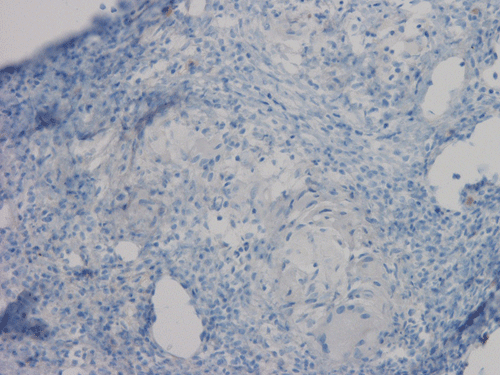

Pathology of the Case: At low magnification, a few small nodules (arrow in Panel A) can be seen with the hematoxylin and eosin stained section. On medium magnification, these nodules correspond to sharply defined granuloma without necrosis. These granuloma are not associated with a high density of lymphocytes in the surrounding liver parenchyma (Panel B and C). Multinucleated giant cells (arrow in Panel C, magnified in Panel D). On reticulin stain, there are reticulin fibers that extends into the granuloma (Panel E). Trichrome stain demonstrated bridging fibrosis (Panel F). The granuloma are well defined and some of them are surrounded by fibrous tissue (Panel G). Immunohistochemistry demonstrated preservation of bile ductules as well as proliferation of ductules (Panle H). No residual ductules are noted in the granuloma as revealed by immunohistochemistry for CK7 (Panel I). Neither acid fast bacilli or fungal organisms are identified by acid fast stain and Gomori's methenamine silver (GMS) stain.

Histopathologic features of sarcoidosis include scattered granulomas in the liver, which may tend to be portal or periportal. Multinucleated giant cells, epithelioid cells, and a variable but usually minimal inflammatory cellular response is present. The granulomas, like in sarcoidosis occuring in other organ systems, tend to be well-demarcated or "clear cut", several granulomas are often comparable in size, and necrosis is not typically present. Asteroid bodies, intracellular vacuolated structures resembling a sea anemone, may be found within the giant cells. Large basophilic, round to roughly oval, and concentrically laminated, Schaumann bodies may be evident in the sarcoid granuloma. None of these inclusions are pathognomonic feature of sarcoidosis, however, do suggest this diagnosis. Ductopenia, cholestasis and features of chronic cholestasis resembling PBC have been described in the cases of sarcoidosis. Severe fibrosis and cirrhosis in conjunction with portal hypertension may be present in sarcoidosis. End stage liver disease in sarcoidosis has been successfully treated by orthotopic liver transplant and recurrent disease has been reported in one such case. Reticulin fibers has a tendency to extend into the granulomas as illustrated in this case.